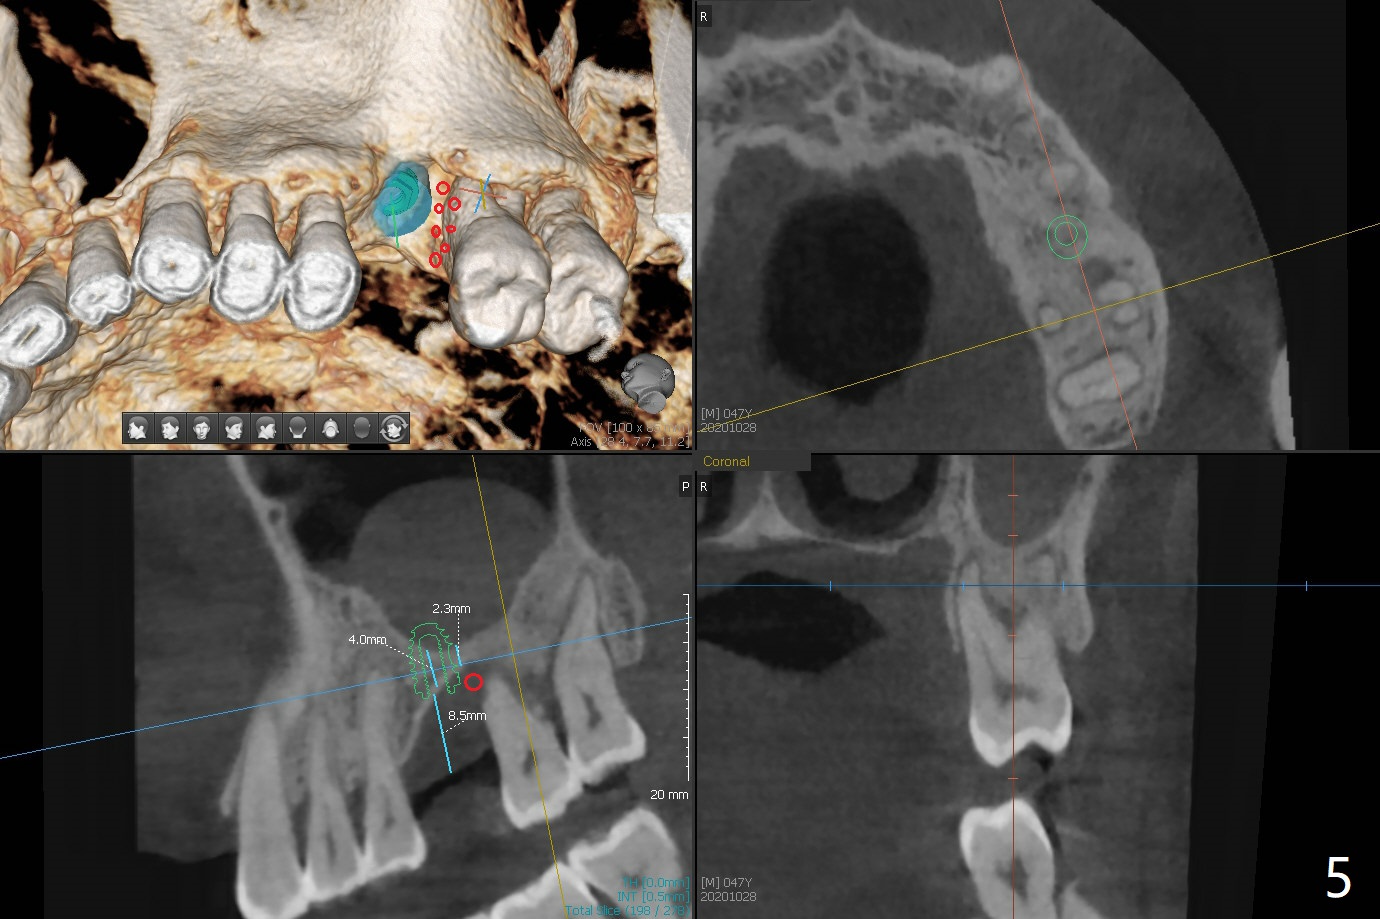

47岁男(吸烟一天半包)因右下8疼痛就诊,口服抗生素疼痛消失,不愿意拔除,但是要求左上6植牙(图一),左上颌窦好像有粘液囊肿(图一,三:*),而右侧上颌窦粘膜更厚(图二)。左上6植牙床是一个斜面,植牙会远中偏移,导板设计应有意往近中(图三:红线)。植体远中根尖需要内提升,冠部需要植骨(图四),厚的粘骨膜有利于植骨(粘骨,使用mill abutment),骨粉尽可能放置7牙根近中(图五:红色圆圈,Endogain)。第二种设计(图六)使用细长植体,近中龈下4毫米,远中龈下8毫米,有利于植骨,覆盖远中暴露的螺纹。Return to No Caries 位点保存/导板 手术 提升 Xin Wei, DDS, PhD, MS 1st edition 10/28/2020, last revision 04/04/2021